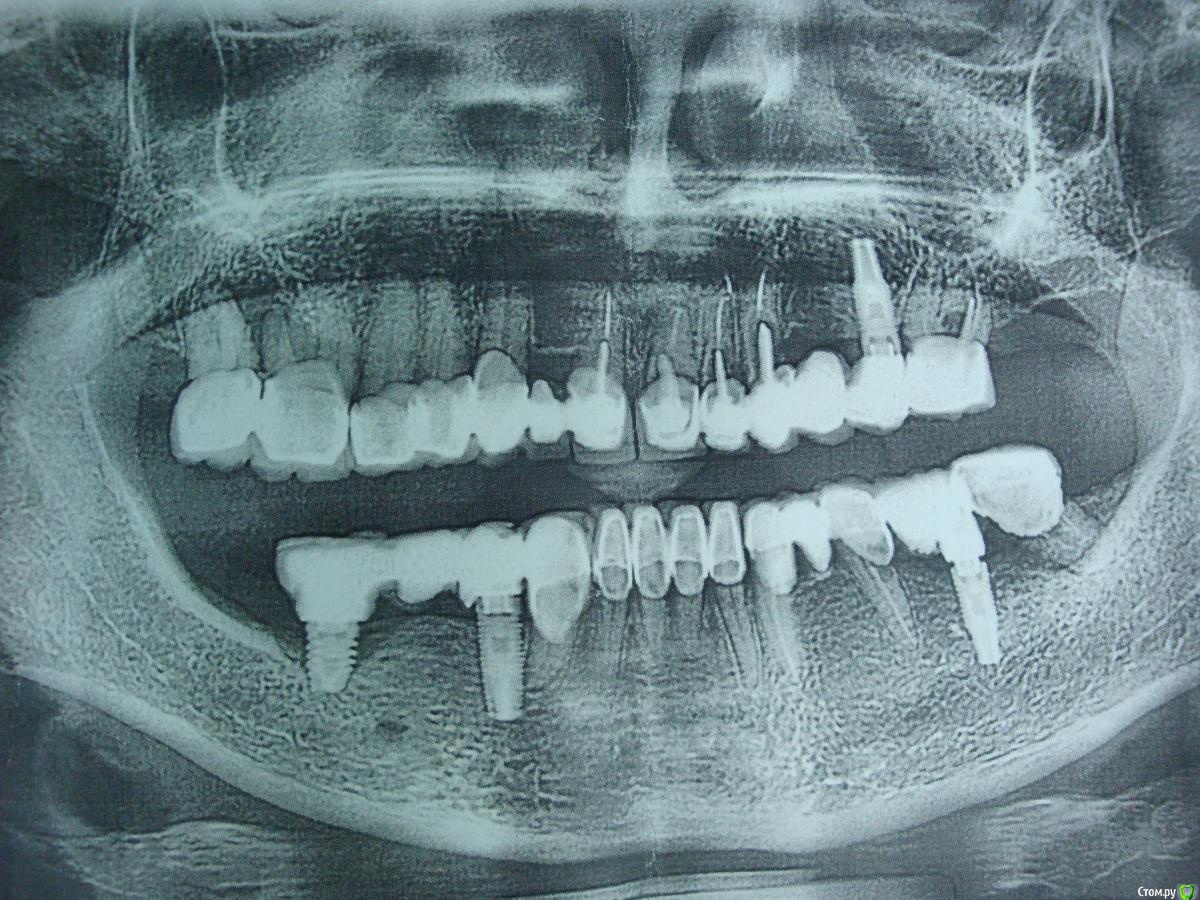

gum Опубликовано 15 июня, 2016 Поделиться Опубликовано 15 июня, 2016 Коллеги подскажите что за система? Ссылка на комментарий

faity Опубликовано 15 июня, 2016 Поделиться Опубликовано 15 июня, 2016 На нобель похоже, груви 3 сегмент, реплейс 4 сегментwhatimplantis.com в помощь Ссылка на комментарий

red_butler Опубликовано 15 июня, 2016 Поделиться Опубликовано 15 июня, 2016 Нее, это не нобель Ссылка на комментарий

gum Опубликовано 16 июня, 2016 Автор Поделиться Опубликовано 16 июня, 2016 biomet 3 i м.б.? Ссылка на комментарий

EdGein Опубликовано 16 июня, 2016 Поделиться Опубликовано 16 июня, 2016 Alpha Bio? Ссылка на комментарий

gum Опубликовано 16 июня, 2016 Автор Поделиться Опубликовано 16 июня, 2016 Нет это не альфа. Ссылка на комментарий

gum Опубликовано 25 июля, 2016 Автор Поделиться Опубликовано 25 июля, 2016 Всем привет, на сайте соответствия не обнаружил, пациентка выяснить название системы не может, клиники той уже нет, м.б. кто-то знает систему? Пациентка уже готова для дальнейшего протезирования, а система не известна. Формирователь от Semados подошел, но вряд ли подойдет абатмент. Ссылка на комментарий

gum Опубликовано 28 июля, 2016 Автор Поделиться Опубликовано 28 июля, 2016 Всем здравствуйте. Ура узнал систему это BTIТеперь вопрос номер два: Кто работал на этой системе, какие ключи от др систем подходят? Кто знает подскажите? Ссылка на комментарий